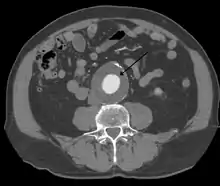

Abdominal aortic aneurysms (3,4 cm)

Abdominal aortic aneurysms (AAAs) are more common than their thoracic counterpart. One reason for this is that elastin, the principal load-bearing protein present in the wall of the aorta, is reduced in the abdominal aorta as compared to the thoracic aorta. Another is that the abdominal aorta does not possess vasa vasorum, the nutrient-supplying blood vessels within the wall of the aorta. Most AAA are true aneurysms that involve all three layers (tunica intima, tunica media and tunica adventitia). The prevalence of AAAs increases with age, with an average age of 65–70 at the time of diagnosis. AAAs have been attributed to atherosclerosis, though other factors are involved in their formation.[7]